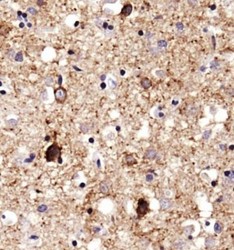

- Immunohistochemistry: SERF1A Antibody [NBP1-78392] - Analysis of SERF1A in human Alzheimer's brain using DAB with hematoxylin counterstain.